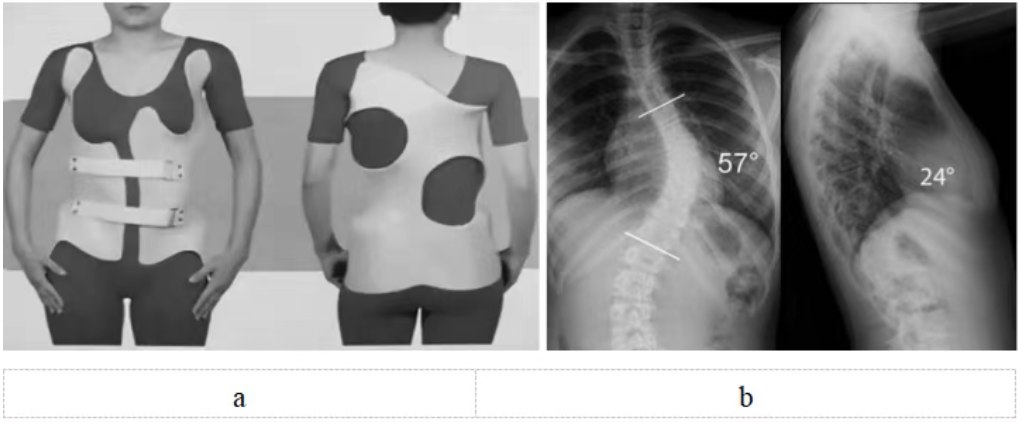

脊柱側(cè)彎支具治療需專業(yè)定制(圖5),日用型每天佩戴20小時以上,夜用型需整晚佩戴。初期可能有不適,需1~2周適應期,要注意皮膚護理。必須堅持佩戴至骨骼發(fā)育成熟,通常需要2~3年。矯正效果取決于佩戴時長和持續(xù)性,家長要做好監(jiān)督。

圖5 a:特發(fā)性脊柱側(cè)彎(中度)配戴支具正面觀和背面觀;b:特發(fā)性脊柱側(cè)彎(重度)X線正側(cè)位,需要手術治療。注:a和b非同一患者

重度側(cè)彎(Cobb角>40度)(圖5):